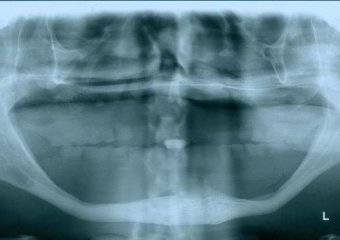

Raio - x Panorâmico inicial, em Julho de 2015